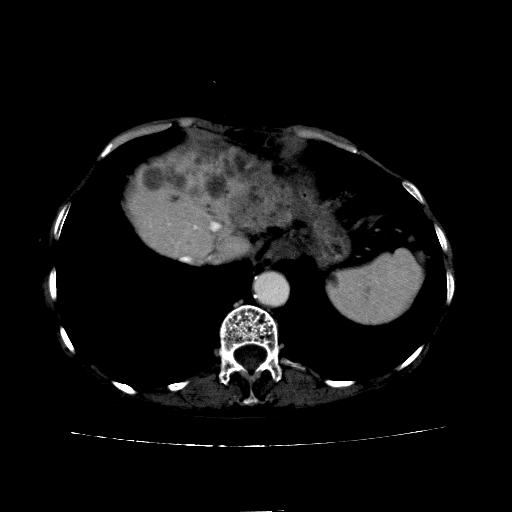

静脉期

考虑胆管结石伴左肝内胆管扩张,不除外胆管细胞癌。

1)考虑肝左叶胆管细胞癌并肝内转移。2)肝左叶肝内胆管结石。